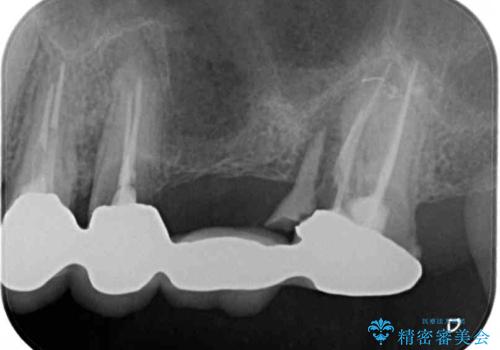

診査の結果、左側は奥歯2本、右側は1本の抜歯が必要であることが分かりました。

左側は大臼歯2本と小臼歯1本が欠損しているため、インプラント2本を治療したブリッジ、右側は中間欠損であり、前後の歯も加療が必要であったためブリッジによる補綴治療を行うこととしました。

抜歯となった歯は全て神経が抜かれた歯であり、強大な咬合力によって破折したことが原因で抜歯となりました。